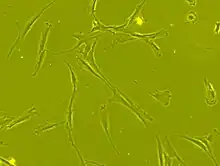

Mesenchymal stem cells (MSCs), a term first named by Arnold I. Caplan in 1991,[5] are characterized morphologically by a small cell body with a few cell processes that are long and thin. While the terms mesenchymal stem cell (MSC) and marrow stromal cell have been used interchangeably for many years, neither term is sufficiently descriptive:

Morphology

The cell body contains a large, round nucleus with a prominent nucleolus, which is surrounded by finely dispersed chromatin particles, giving the nucleus a clear appearance. The remainder of the cell body contains a small amount of Golgi apparatus, rough endoplasmic reticulum, mitochondria, and polyribosomes. The cells, which are long and thin, are widely dispersed, and the adjacent extracellular matrix is populated by a few reticular fibrils, but is devoid of the other types of collagen fibrils.[11][12] These distinctive morphological features of mesenchymal stem cells can be visualized label-free using live cell imaging.